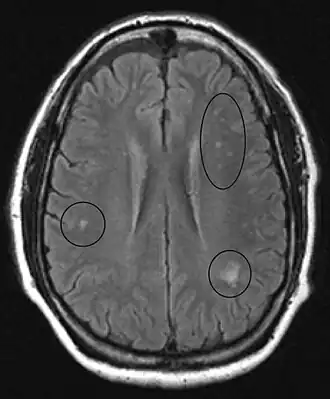

In the brain itself, changes are less severe: They occur as small sources of nervous fibers decay and accumulation of astrocytes, usually subcortically located, and also round hemorrhages with a torus of glial cells.

MRI of the brain may show periventricular white matter abnormalities. MRI of the spinal cord may show linear hyperintensity in the posterior portion of the cervical tract of the spinal cord, with selective involvement of the posterior columns.